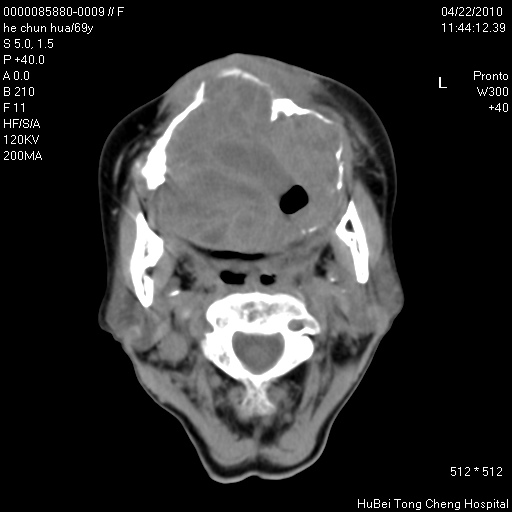

标题: CT25937:女,69Y

硬腭部包块十余年,渐进性增大。

病程长,考虑巨细胞修复性肉芽肿可能性大;

鉴别:神经源性病变、硬结病等。

五楼说得有道理,支持一下。巨细胞修复性肉芽肿好象是外伤出血后引起的修复性改变,骨质呈溶骨性破坏,但病程呈良性过程。